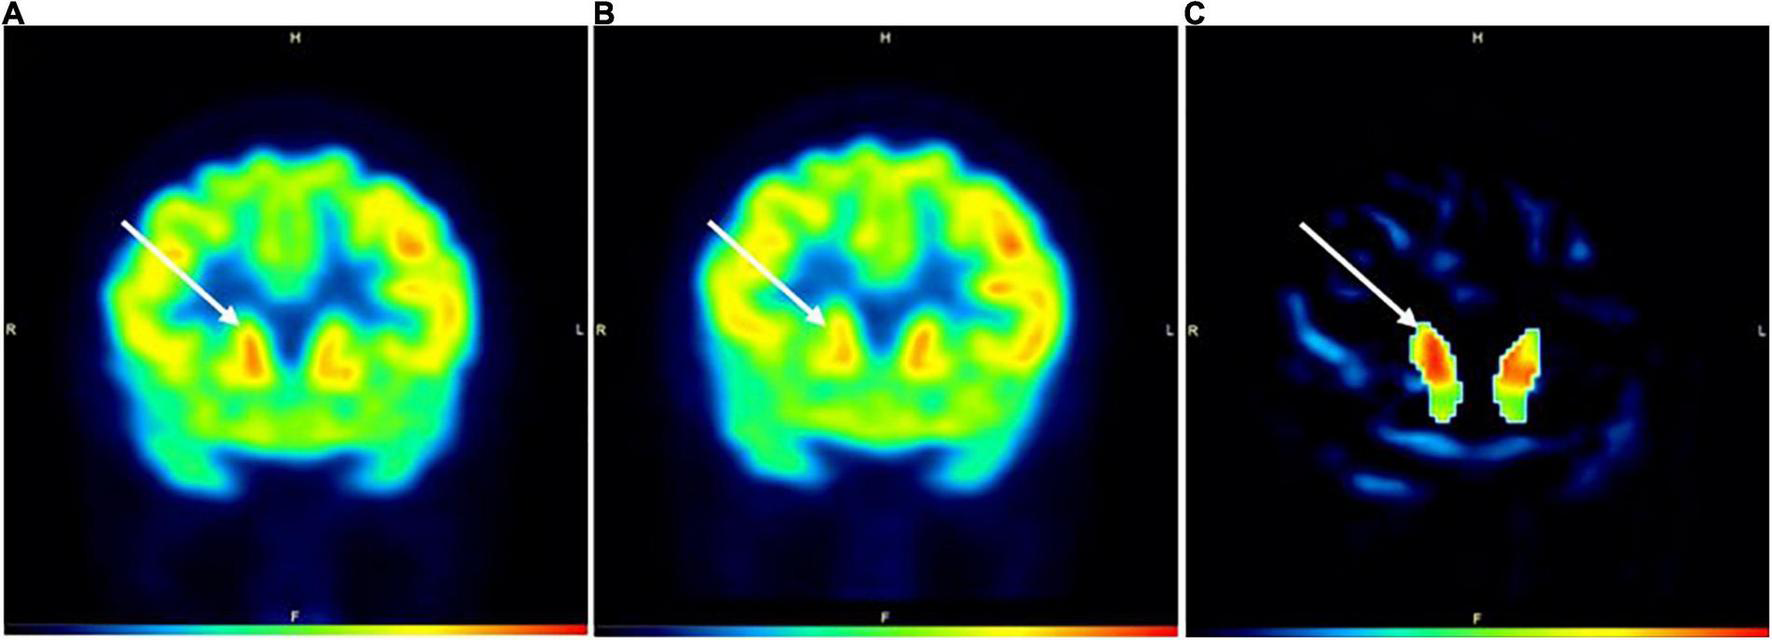

In Subject 3, the areas under the anode and cathode showed a modest increase in activity (1.94% – 5.64%; Table 1) in active compared to SHAM, with all areas under the cathode showing at least 3.5% increases in activity. For the basal ganglia, the rt caudate nucleus displayed an 8.68% increase, the lt substantia nigra, rt putamen, and lt putamen all had >4% increase in activity, and the rt substantia nigra was the only area that showed a decrease in activity (−7.38%) in active compared to SHAM (Table 1 and Figure 2).

FIGURE 2

PET images during active (A) and SHAM (B) conditions in Subject3. Image (C) represents a subtraction PET image with the globally normalized activity in sham subtracted from the globally normalized activity in active. All areas in image (C) are masked except for the caudate nuclei. White arrows denote the location of the caudate nuclei. The color bar indicates level of increased FDG uptake (black = no uptake; red = highest glucose uptake). H = head; F = foot; R = right; L = left.